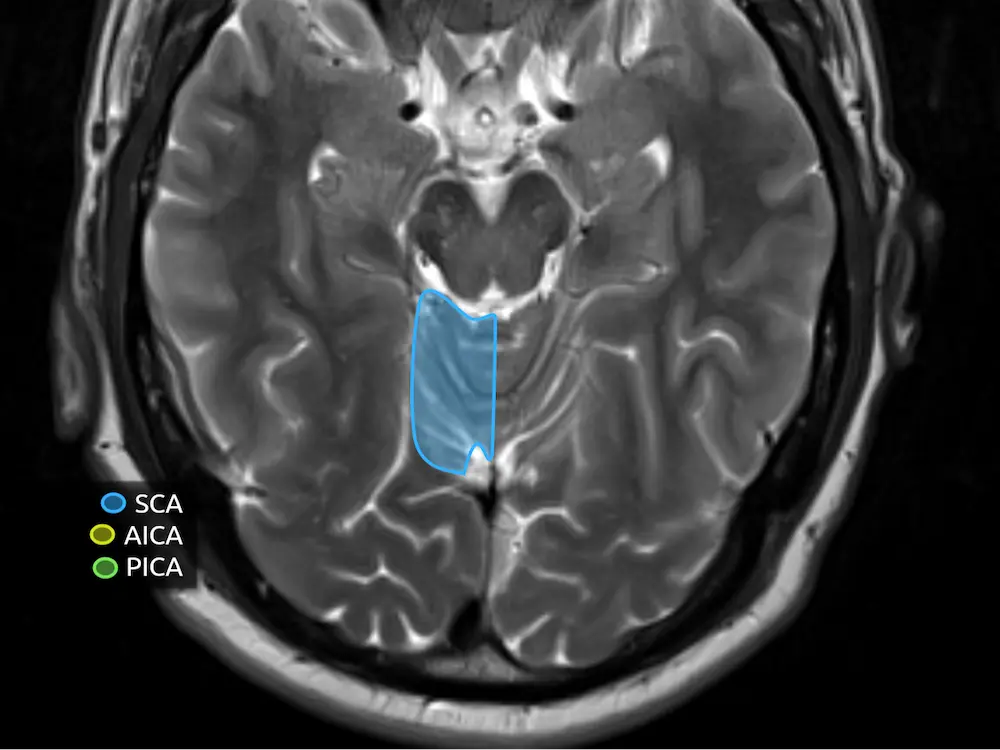

The cerebellum receives arterial supply from the posterior circulation (Figure 7). Above the level of the middle cerebellar peduncles, the majority of the cerebellum is supplied by the superior cerebellar artery (SCA). Below, the majority is supplied by the posterior inferior cerebellar artery (PICA). The anterior inferior cerebellar artery (AICA) has a smaller contribution, supplying the middle cerebellar peduncles and the flocculus. Note the AICA does not classically contribute to the vermis.

In reality, the boundaries of these territories are not so clear cut and there is significant variation. The AICA and PICA are in balance with each other, such that a patient with a small PICA will have a larger AICA that supplies a larger portion of the inferior cerebellar hemispheres (i.e. AICA-PICA balance or AICA-PICA dominance). There is also a balance of supply to the vermis between the SCA and PICA.